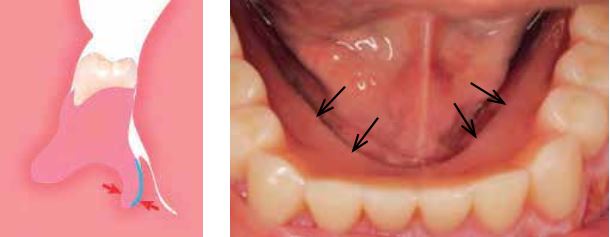

Xác định vị trí của lưỡi khi há miệng

Việc há miệng thường đi kèm với một sự co nhẹ của lưỡi. Ít nhất 75% dân số có hiện tượng này. Ở 25% còn lại, có thể quan sát thấy sự co mạnh hơn một chút (loại 2) hoặc co rõ rệt hơn nhiều (loại 3). Hậu quả là không khí dễ dàng lọt vào bên dưới nền hàm giả và làm hàm bị bật ra.

Loại 2 và 3 là những trường hợp khó xử trí vì không thể đạt được một đường viền kín hoàn toàn. Trong các trường hợp này, cần sử dụng kỹ thuật lấy dấu đặc biệt được xây dựng dành riêng cho các ca khó.